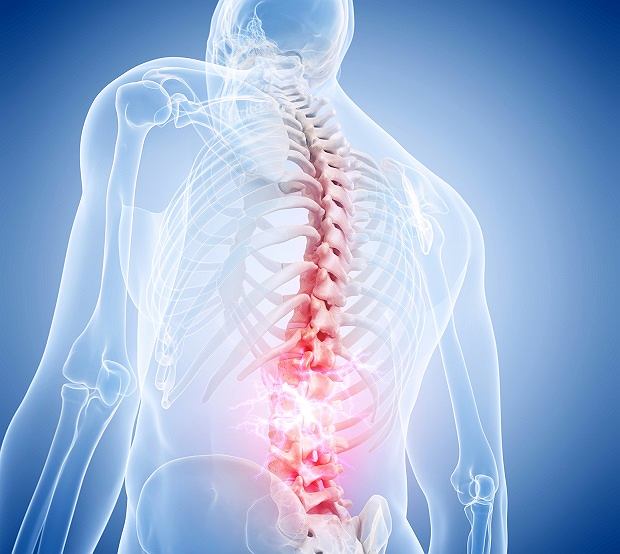

Przejdź do oddziału SiedlceMasz ból kręgosłupa, barku lub kolana?

Pomagamy w dolegliwościach bólowych i ograniczeniach ruchu – od diagnostyki funkcjonalnej po indywidualnie dobraną terapię i ćwiczenia.

Kręgosłup i napięcia mięśniowe

Terapia bólu pleców, przeciążeń, ograniczeń ruchu oraz profilaktyka nawrotów – bezpiecznie i skutecznie.